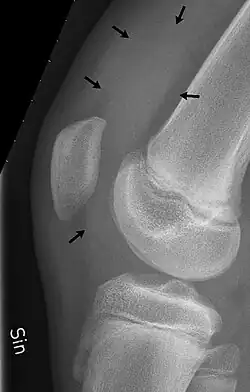

X-Ray skyline view of the patella demonstrating a large joint effusion as marked by the arrow

X-Ray

An X-ray may be recommended by your provider as a way to obtain a 2-dimensional image to visualize the joint in question. In the presence of trauma an X-ray can be especially useful to verify that there is no break, dislocation, or deformity. In an atraumatic knee, an X-Ray can be used to identify or rule out other causes of a knee infusion including some inflammatory or age-related causes.

X-ray of the knee of a 12-year-old male, showing knee effusion of medium severity, marked by black arrows. It displaces the patella anteriorly and extends into the suprapatellar bursa.